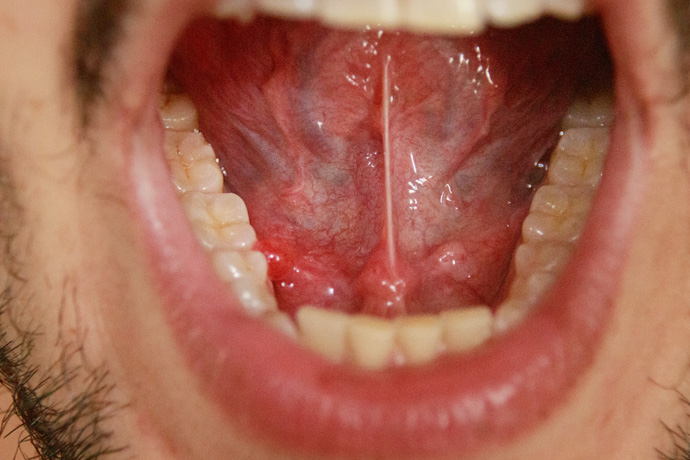

Las ránulas son un tipo de quiste lleno de saliva que se forma debajo de la lengua, tal y como mencionamos en la introducción. Según Cleveland Clinic, pueden existir dos tipos de ránula: simples y hundidas.

Las ránulas simples causan una inflamación limitada a la boca; por otra parte, las ránulas hundidas tienen un efecto negativo mayor, y la inflamación se puede extender incluso hasta el cuello.

- Ránula simple (u oral): este tipo de ránula se produce cuando el quiste que se forma por la acumulación de saliva se aloja debajo de la lengua. En general, no causa dolor, pero sí puede generar molestias al hablar, comer o deglutir, especialmente si crece y ocupa más espacio en la cavidad bucal.

Una buena forma de reconocerlas es prestar atención a sus características, ya que suelen aparecer como un bulto transparente o azulado debajo de la lengua. Pueden tener entre 5 y 7,5 cm de diámetro, y muchas veces se vacían y se vuelven a llenar.